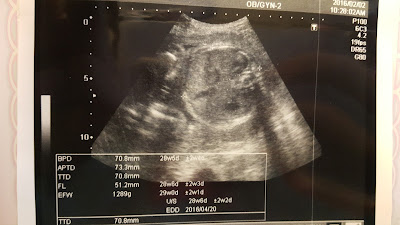

這是過年前的產檢文

時間很快滴,邁入第7個月了

說看別人懷孕、帶小孩好像日子過的很快